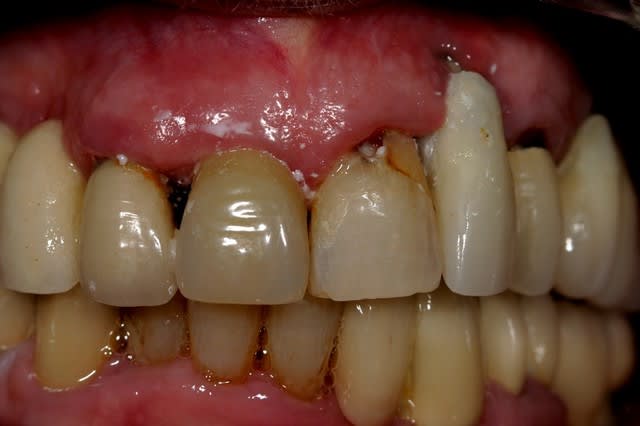

Voilà. Cette patiente se présente à moi. Elle est suivi depuis assez longtemps par un stomato. Qui l'a pris en charge pour la pose des implants que vous voyez sur la Pano.

Depuis deux ans cette patiente perd sa couronne sur 11. Vu l'état de la racine cela se comprend. Son praticien (sto) lui rescelle a chaque fois lui disant que l'on va s'en occuper...et cela tiens quelques jours au mieux.

Les implants maxillaire sont sous provisoires depuis au moins 8 mois. La dernière fois que j'ai vu la patiente je lui ai dit que l'on peut soir envisager un implant en position de 11, ou envisager un bridge 12-11-21 Car je pense que esthétiquement ce sera plus jouable...

Je l'ai informé qu'elle avait un gros soucis de carie sous les dents 47-46-45...Et que cela allez poser problème rapidement, mais que le site était propice au implants...

Le conjonctif sur la 22...je vois pas comment ça pourrait prendre je vois presques des spires de l'implant...

intéressants, les implants zygomatiques qui s'arrêtent au quart du chemin. d'un point de vue biomécanique, ce traitement implantaire, c'est n'importe quoi. les édentements terminaux à droite et à gauche doivent être soutenus par 3 implants minimum, de préférence ostéo-intégrés, et de préférence pas dans la cavité sinusienne (il se peut que les implants soient placés dans une paroi sinusienne en évitant la cavité, mais je doute). la ligne de gencive sur l'implant en 22 est irrécupérable, car il n'y a rien pour soutenir une greffe. ce que je ferai: